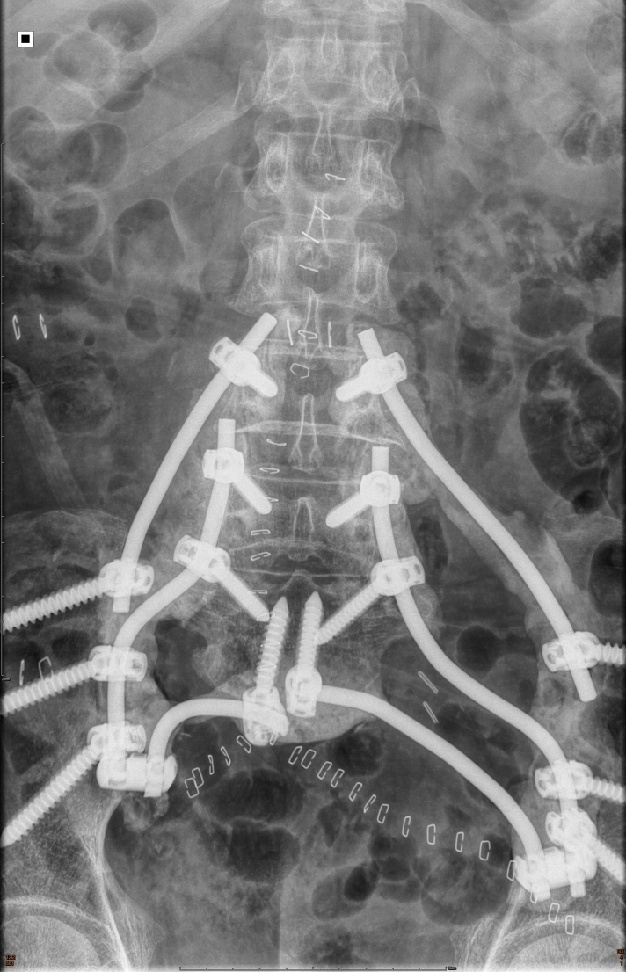

随后,由尹军强教授主刀行后路全骶骨+左侧髂骨精准切除。通过超声骨刀精准截骨,分离安全的肿瘤边界,将肿瘤彻底切除。紧接着,医生团队根据术前设计的重建方案,在骨科机器人辅助下利用腰椎钉棒内固定系统,将腰椎与骨盆连接起来,恢复患者脊柱与骨盆的骨性连接。

术后患者脊柱与骨盆成功连接